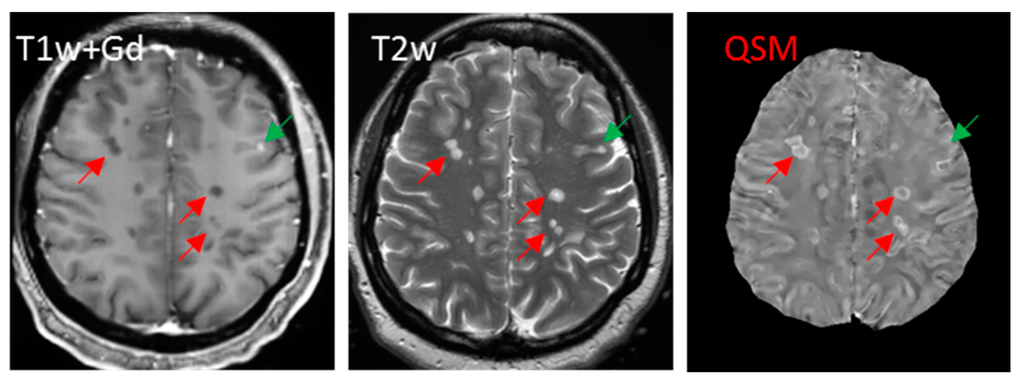

Iron in white matter lesions can be identified at the hyperintense rim on QSM, in the QSM lesion volume lying outside the lesion volume on T2-weighted imaging, or with the positive QSM value relative to the CSF [41,147,181,182] (Figure 6). The myelin contribution to susceptibility may be compensated using quantitative myelin water fraction imaging and diffusion tensor imaging, providing absolute iron quantification in general.

Figure 6.

Non-enhancing lesions appear larger with hyperintense rim on QSM (red arrows) than on T2w, while enhancing lesions appear isointense on QSM (green arrow).

Using QSM and T2w together can allow for accurate identification of lesions in MS patients without Gd injection (Figure 6), utilizing the fact that the magnetic susceptibility of an MS lesion increases rapidly as it changes from Gd-enhancing to non-enhancing [42]. We performed a preliminary study with the following findings [185]: a total of 126 new lesions were evaluated in 52 patients. Eighty-three lesions were identified as Gd-enhancing with their susceptibility values (2.46 ± 6.40 parts-per-billion (ppb)) significantly lower than those of non-enhancing lesions (19.92 ± 7.80 ppb, p < 0.005). Receiver operating characteristic (ROC) analysis for discriminating enhancing and non-enhancing lesions using susceptibility values showed an area-under-the-curve of 0.956. A cutoff-value of 11.2 ppb for QSM-measured susceptibility provided a sensitivity of 89.2% and specificity of 90.7%. Therefore, QSM can be used in routine MRI monitoring of new MS lesion activity to accurately identify the BBB leakage status of T2w lesions without gadolinium injection, which would be useful particularly for MS patients with contraindications for Gd injection.